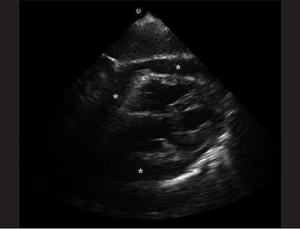

Ultrasound

- Pericardial effusion

- In acute cases, even a relatively small build up of pericardial fluid can lead to hemodynamic compromise

- Diastolic collapse of the right atrium (in atrial diastole)

- Diastolic collapse of the right ventricle

- Plethoric IVC

- Valvular pulsus parodoxus

- Doppler interrogation across the mitral valve will demonstrate exaggerated respiratory variability of transvalvular flow